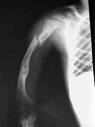

Hueso fracturado por la Osteogénesis ImperfectaLa epidemiología es la ciencia que estudia los patrones de la enfermedad a nivel de variaciones geográficas, demográficas, estado socioeconómico, genética, edad y causas infecciosas. Los epidemiólogos estudian la relación entre estos factores así como los patrones de migración y contribuyen a un mayor conocimiento de la enfermedad.

Radiografía de la parte delantera de una personaDensitometría ósea

Se puede realizar una densitometría, una prueba no invasiva que mide la masa ósea en general o en zonas específicas. Es importante medir la masa ósea de la columna vertebral, en caderas y brazos, porque son las zonas donde más frecuentemente de dan las fracturas, cuando la masa ósea es baja. Otro método utilizado para medir la masa ósea es el DEXA. La densitometría ósea no proporciona un diagnóstico de seguridad de la enfermedad, pero si lo combinamos con la historia médica personal y familiar puede ayudar bastante. La densidad del hueso puede ser normal en las personas con poca afectación.

La densitometría puede ser muy útil para ver el desarrollo de la enfermedad y determinar la probabilidad de fracturas. También puede ser útil para evaluar los posibles efectos adversos de la medicación o de las lesiones que se produzcan.

Algunas medidas DEXA pueden resultar engañosas debido a las deformidades esqueléticas (curvatura de la columna vertebral, fracturas de compresión en vértebras o el metal ortopédico) o por la estatura del paciente. El DEXA es una prueba muy poco agresiva, pues aunque utilice rayos x, la irradiación es sumamente baja (el 10% de una radiografía de tórax).

Las personas que más se pueden beneficiar de estas pruebas son las pertenecientes al tipo I, pues tienen una vida más larga y tendrán que afrontar la pérdida de hueso asociada a la menopausia, la inmovilización o la medicación. En otros tipos de Osteogénesis Imperfecta, la densidad de hueso puede ser muy baja y el manejo de la enfermedad muy difícil. La densitometría se suele realizar una vez al año en los adultos

En muchas ocasiones, las micro - fracturas no son visibles a rayos x inmediatamente después de la lesión, y se hacen visibles cuando se forma el callo de fractura una o dos semanas más tarde

En la mayoría de las personas afectadas de Osteogénesis Imperfecta, los rayos x se convierten en una prueba frecuente y necesaria de asistencia al diagnóstico y tratamiento. Hay peligro para la salud con la exposición frecuente a los rayos x, directamente relacionada con la intensidad de estos. Es conveniente guardar un registro con las fechas en las que se le han realizado radiografías.